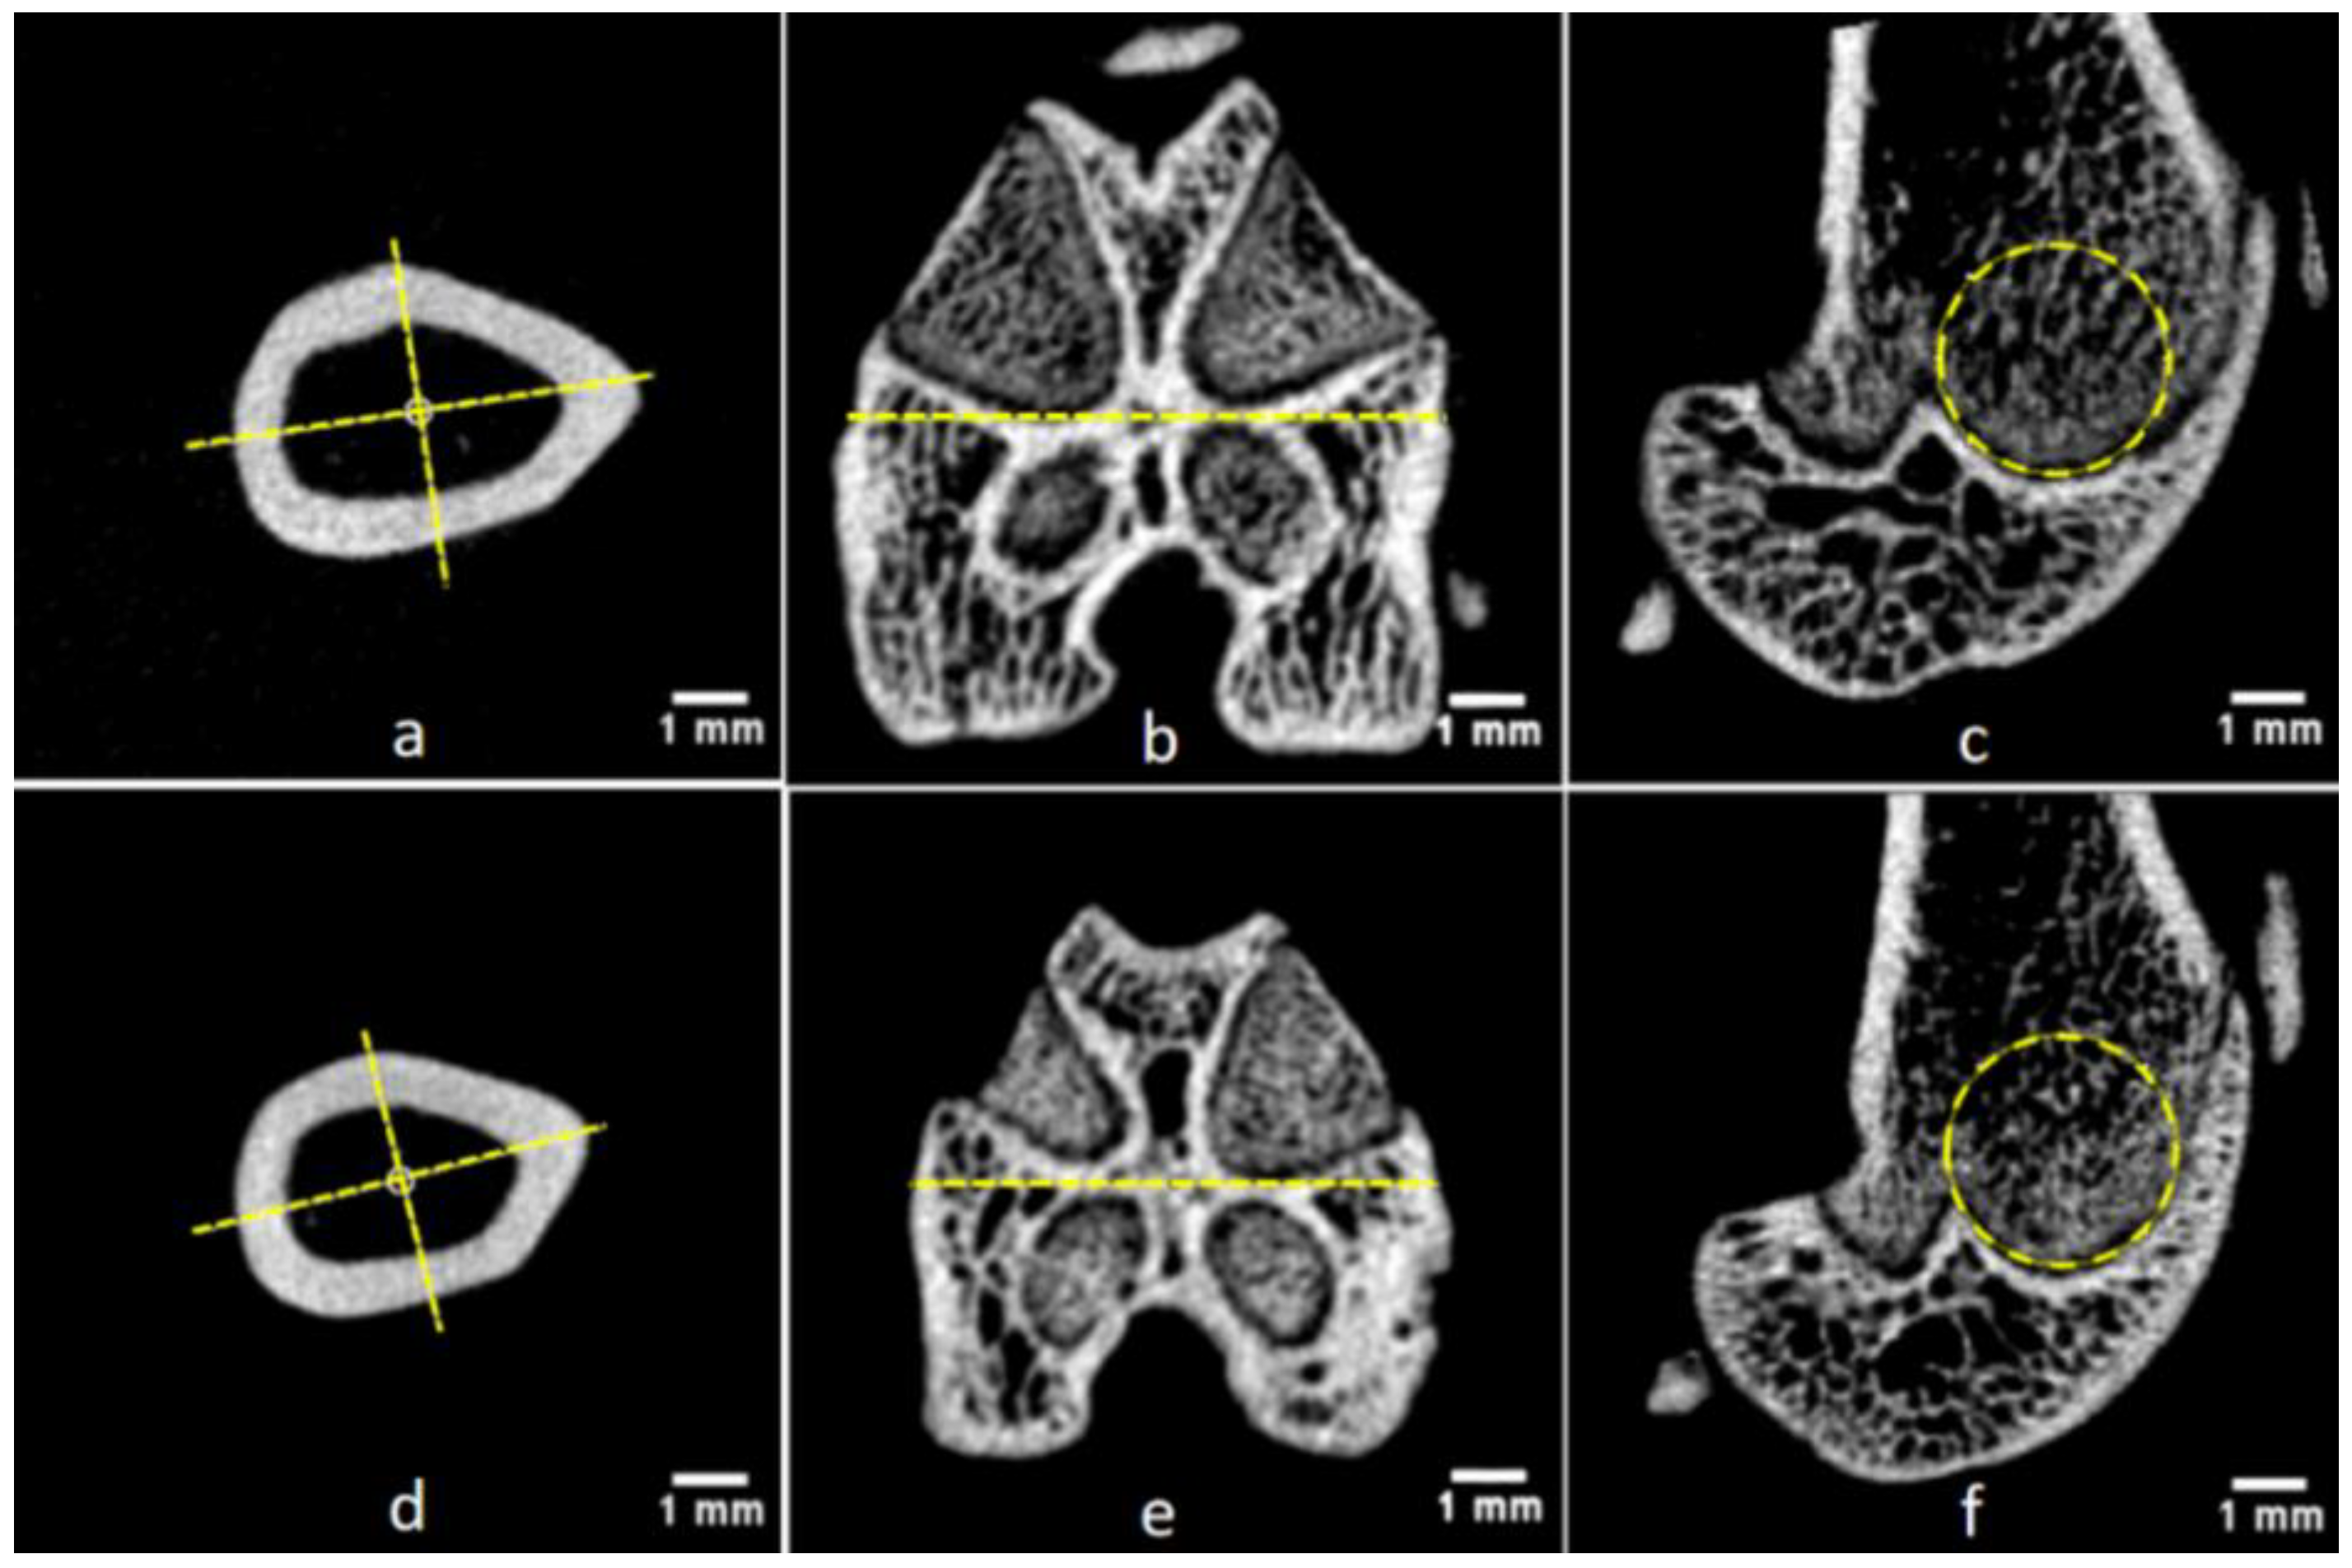

3.4. Detection of Gender-Related Bone Size Difference